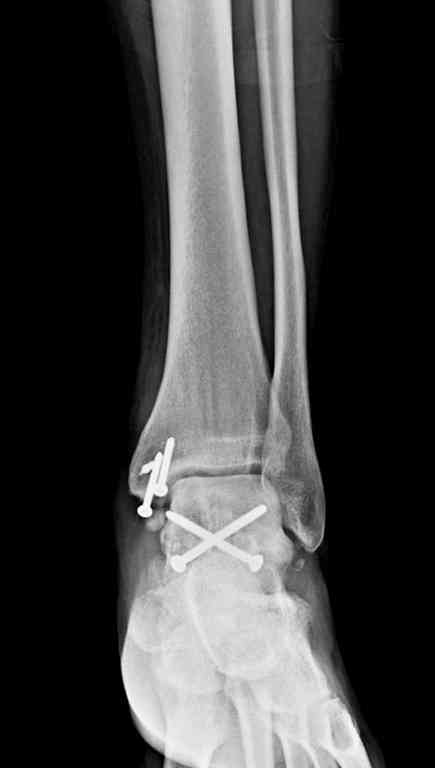

Переломовывих тарана с повреждением медиальной стороны. Через 4 часа после поступления проведена репозиция и фиксация тарана после Irrigation&Debridment. Частичное несращение медиальной лодыжки не беспокоит, вернулся к активному образу жизни. Полная нагрузка разрешена через 11 недель. Финальные снимки через 11 месяцев.